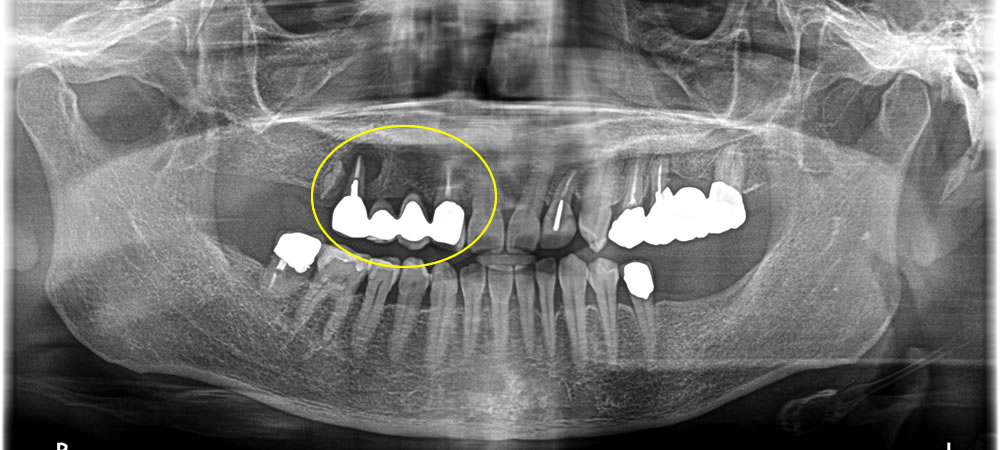

レントゲン撮影での検査の結果、過去に他院で治療されたブリッジの根っこが感染によって膿が溜まり、炎症を起こしてることが痛みの原因であることがわかりました。

ブリッジの奥の歯は抜歯が必要と診断、抜歯後の治療法を相談させていただいたところ、入れ歯は嫌とのことでインプラントをご希望されました。

ブリッジの手前の歯はまだ使うことができると判断し、ブリッジ除去後、一本のかぶせ物にしました。奥の歯は抜歯後、下の歯と奥まで噛み合うように設計し、金額を抑えるため、本来4本分の歯をいれるところをインプラント3本でブリッジにし、4本分の歯を作りました。奥の歯は骨の損傷が大きかったため、抜歯と同時に骨造成も行っています。